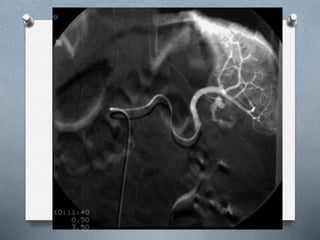

 Arteriografía (rol importante en el manejo

no operatorio de la hemorragia y la

hemobilia)

Angiografía

O No se utiliza de primera elección, pero

cada día se utiliza mas como opción

terapéutica.

O Casi siempre se realiza después de una

TAC, para realizar angioembolización

Angiografía O No seutiliza de primera elección, pero cada día se utiliza mas como opción terapéutica. O Casi siempre se realiza después de una TAC, para realizar angioembolización